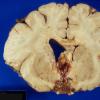

NEOPLASMS (MESENCHYMAL, NON-MENINGOTHELIAL)

Hemangioblastoma (5)